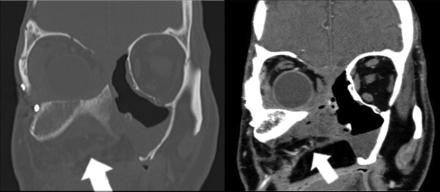

The internal oblique muscle from the flap eliminates the maxillectomy cavity, thereby preventing the presence of dead space (arrows).

Axial imaging of a normal ICFF demonstrating a thick sheet of bone with a hyperattenuated cortex and intermediate attenuation of the trabecular surface. An osteotomy site is demonstrated and filled with corticocancellous bone (arrow). Images were obtained in the immediate postoperative period. Left cheek prominence is an expected immediate postoperative finding in the flap setting. Normal cheek cosmesis will be obtained over time.